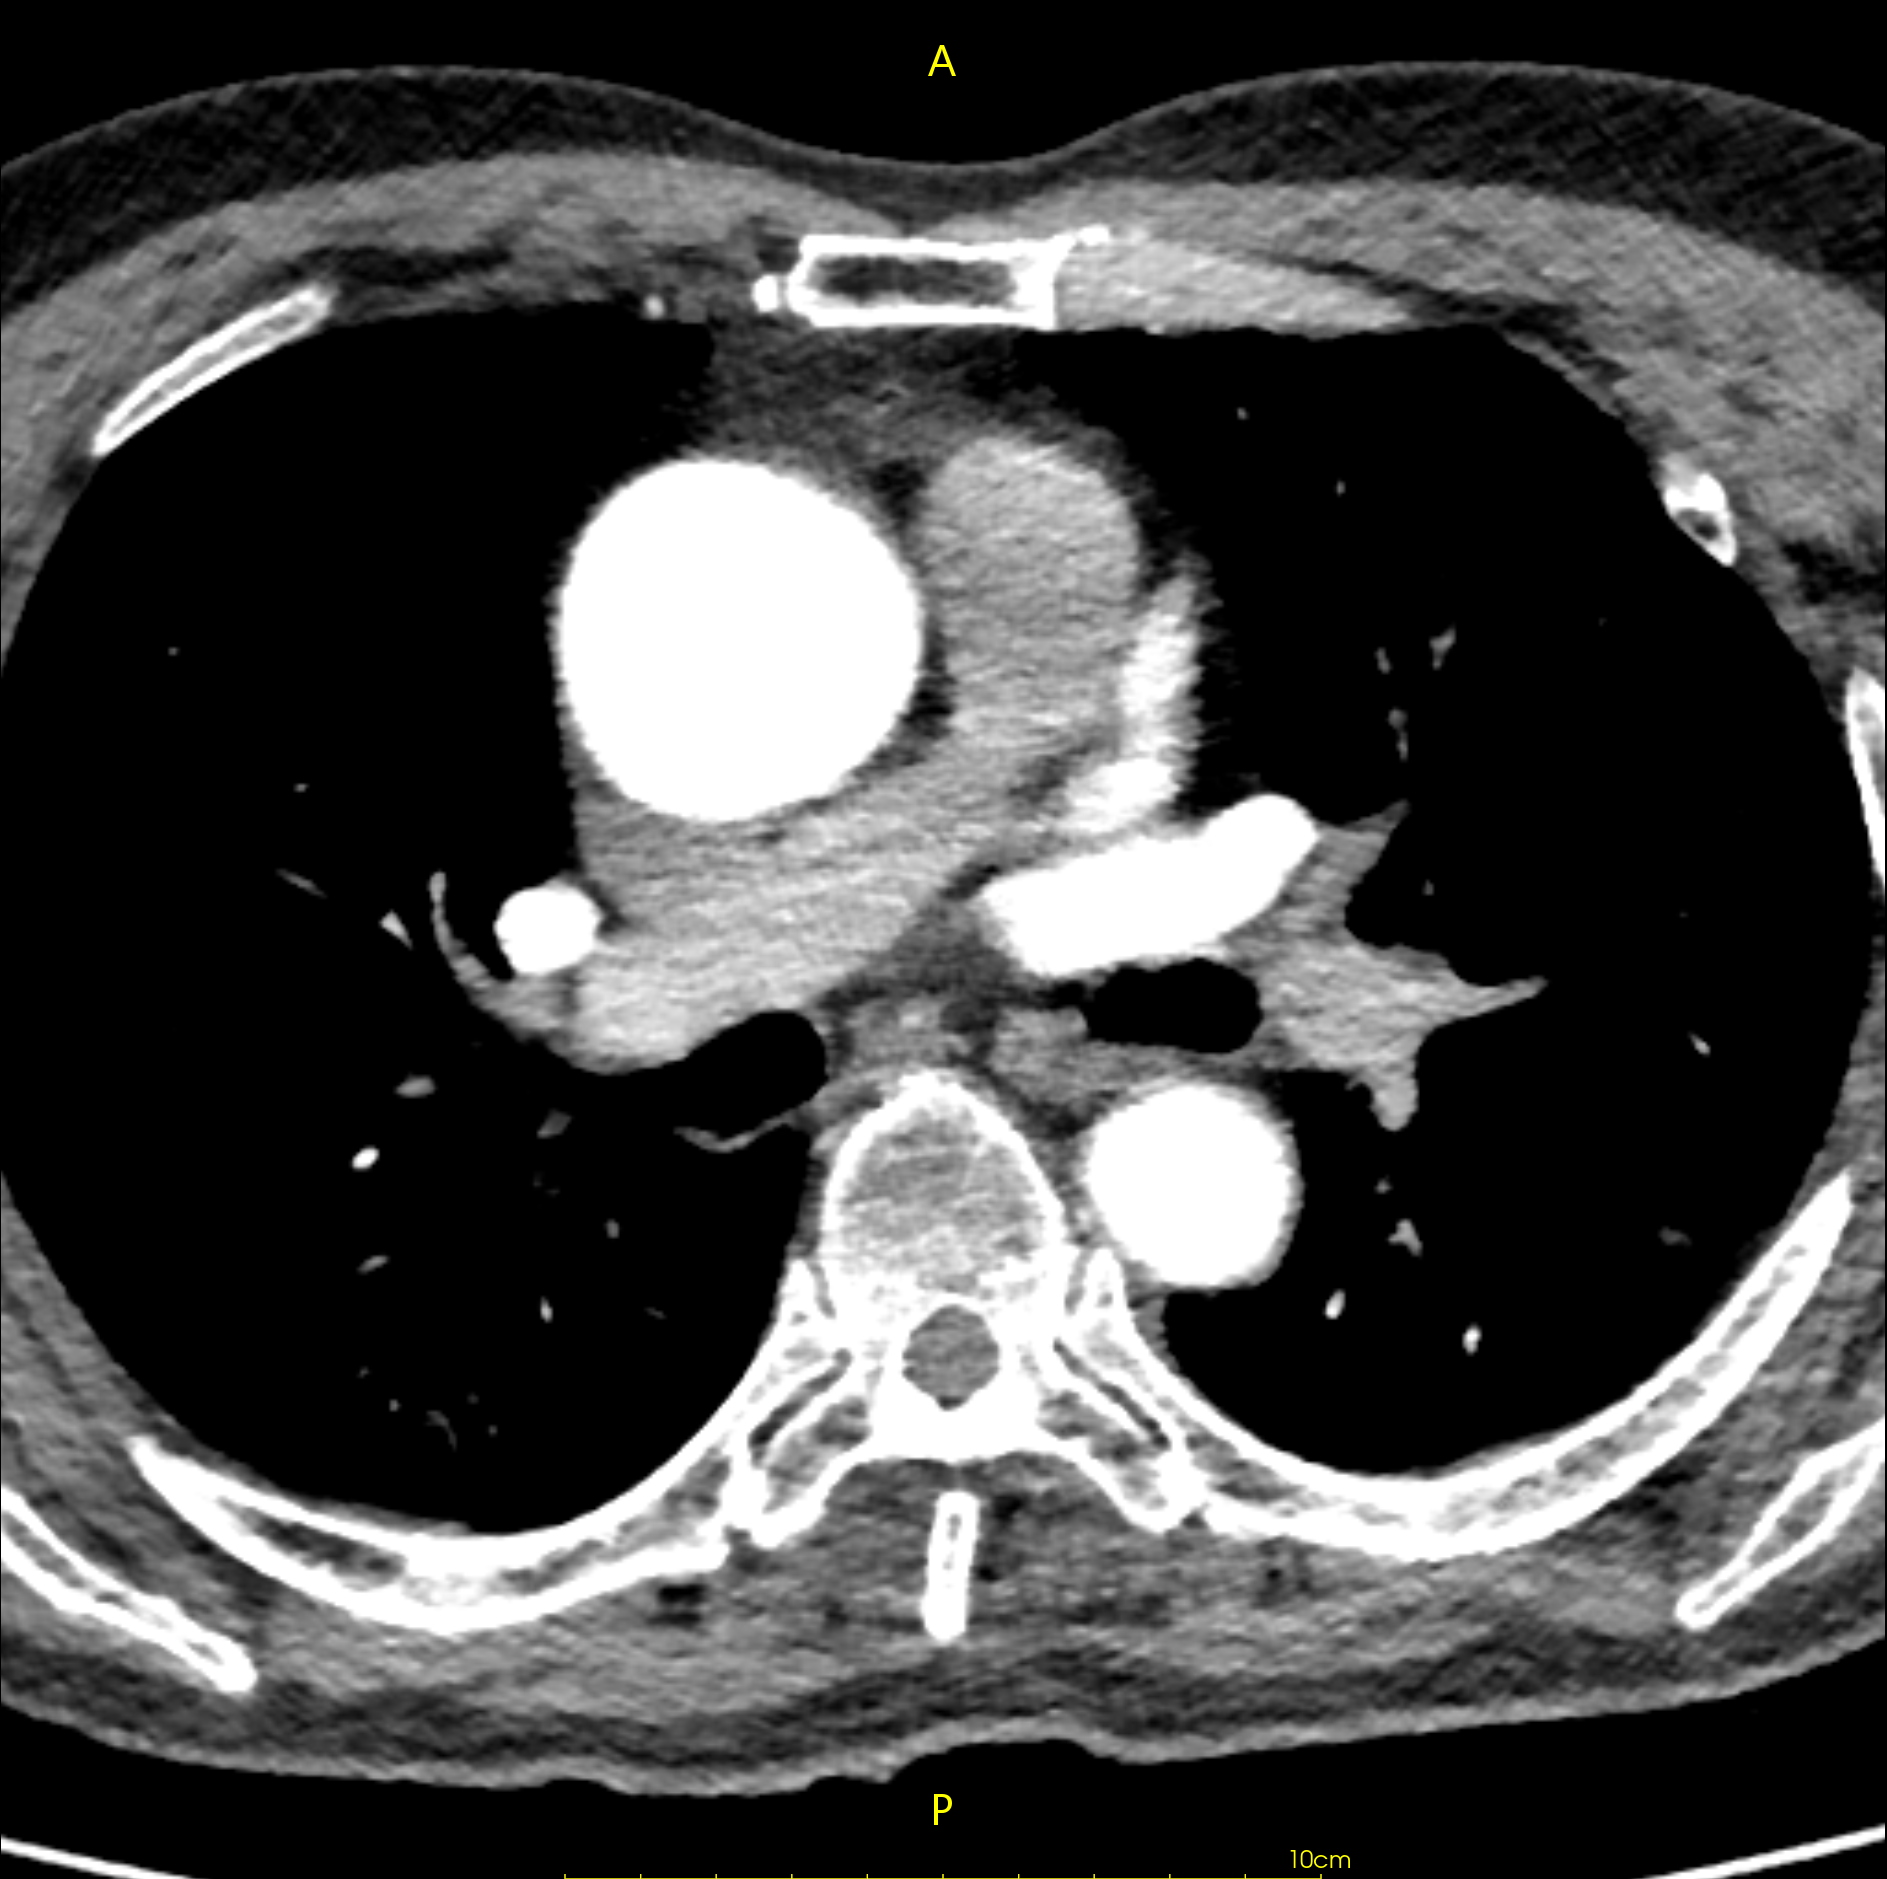

https://blog.csdn.net/liushao1031177/article/details/117696381 如果遇到下面这种有明显边界的ct影像,如何才能区分哪些是有效的CT值,哪些是背景值?

我们可以根据0028,0103内值来区分图像是否被填充过,如果pixel representation为0,则该CT图像未被填充过,其内部像素值都表示有效CT数值;如果pixel representation为1,则该CT图像内有两部分CT值,一部分是有效CT值,另一部分是填充值,只是为了把图像展示成矩形图像;

我遇到的这个数据中,0028,0103为1,则存在0028,0120值,其值为-2000。

我遇到的这个数据中,0028,0103为1,则存在0028,0120值,其值为-2000。

由于图像的斜率为1.0,截距为-1024,则-2000就会在线性变换后为-3024;

找一个背景值,可以看到该值为-3024;则像素值为-3024的像素即为填充像素,可以在后处理中过滤掉;